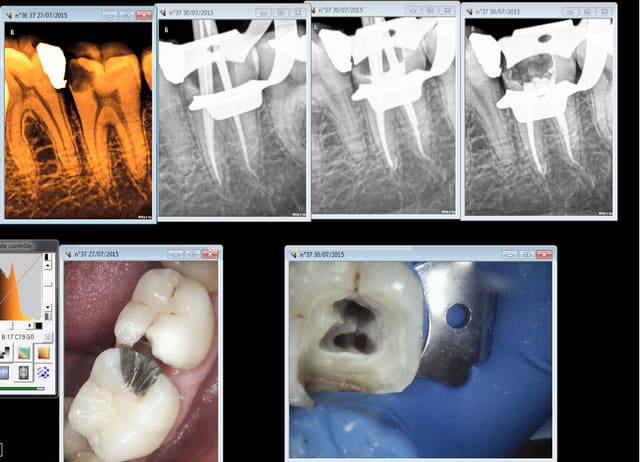

une 37 .......

Capture d e cran 2015 07 30 16.22 - Eugenol

J'en étais resté au thermocompactage: simple, rapide et pas cher et utilisable avec de la gutta "low cost" genre R&S.

L'idéal en dentisterie sécu.

L'irrigation alternée avec Salvizol et hypochlorite permet en plus d'avoir très souvent des puffs comme les pros ...

Inconvénient: il faut impérativement faire un cône d'arrêt à LT-1 et avoir un bon tug back à cette longueur sinon c'est le dépassement assuré.

Il y a parfois des casses de pointes de Mc Spadden comme sur la radio de la 14 mais comme c'est un instrument stérile noyé dans de la gutta ça ne (me) pose pas de problème.